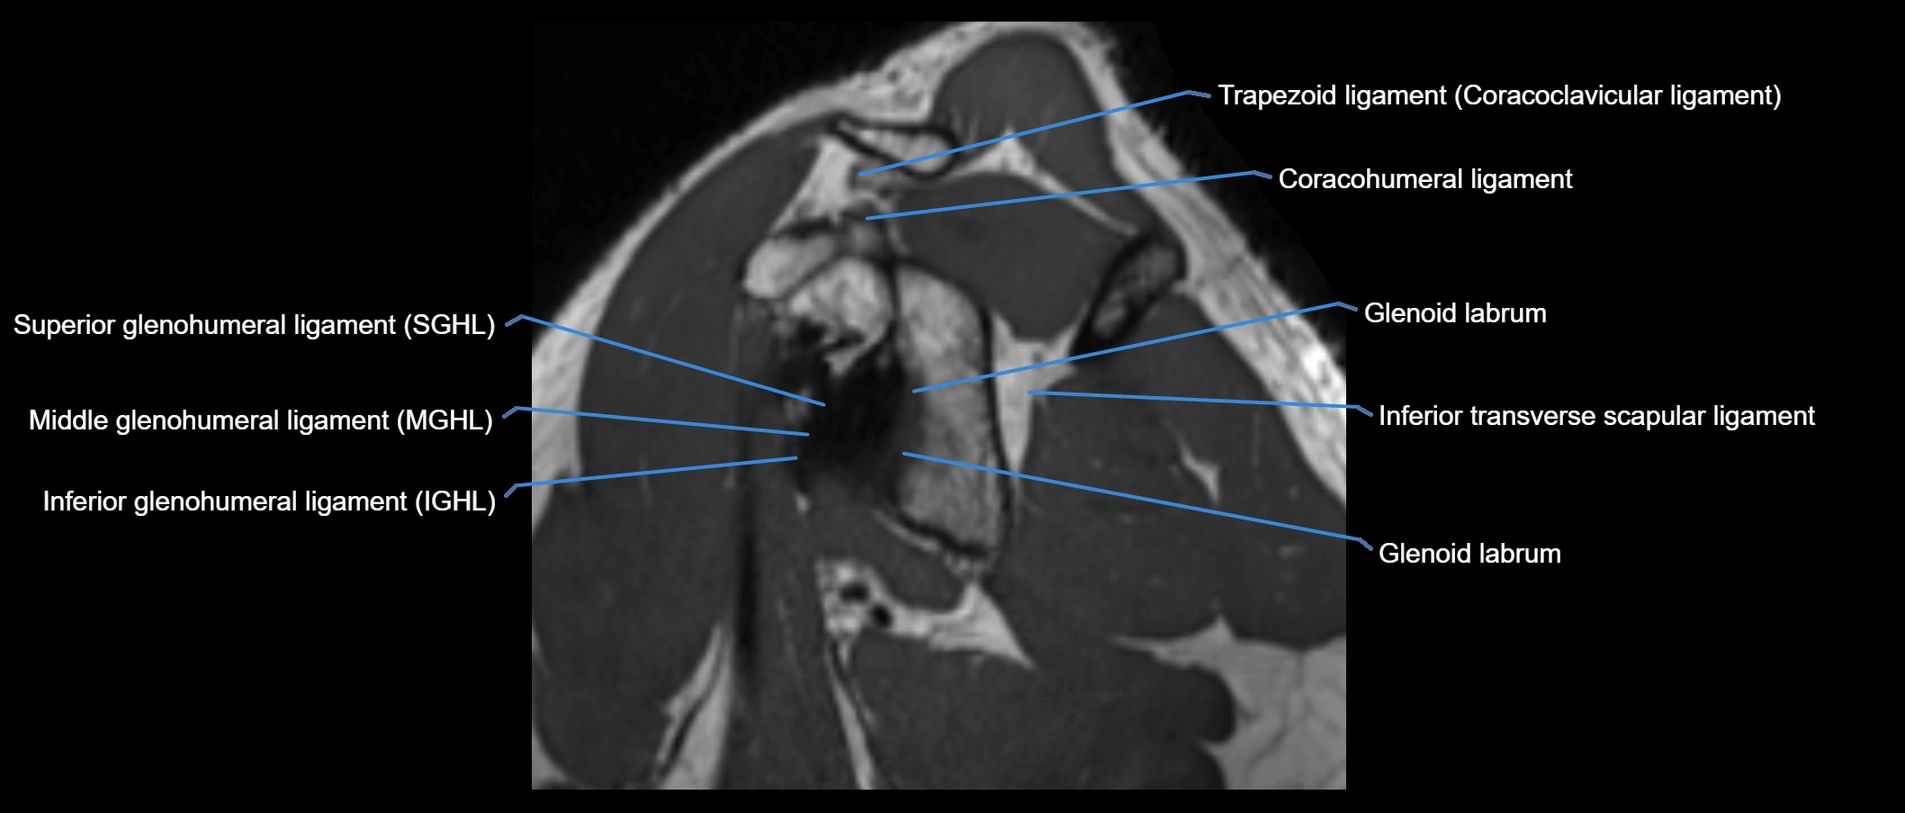

MRI images

image

MRI Appearance

• T1-weighted images:

• Normal ligament: Low signal (dark linear band) spanning acromion to clavicle.

• Surrounding fat planes: Bright, delineating the ligament clearly.

• Marrow of clavicle and acromion: Bright due to fatty content.

• Tears: Discontinuity or irregular thickening with intermediate-to-bright signal.

• Chronic injury: Thinning, fraying, or irregular low-signal fibers with adjacent scarring.

• T2-weighted images:

• Normal ligament: Low signal, homogeneous.

• Partial tear or sprain: Focal hyperintensity or thickening.

• Complete tear: Discontinuity with fluid-bright gap between clavicle and acromion.

• Associated edema: Bright signal in distal clavicle or acromion marrow.

• STIR:

• Normal ligament: Dark linear band.

• Injury or inflammation: Bright hyperintense signal in and around ligament fibers.

• Highlights periligamentous soft-tissue edema, especially in acute trauma.

• Proton Density Fat-Saturated (PD FS):

• Normal ligament: Low signal, uniform thickness.

• Partial tear or sprain: Bright signal or contour irregularity.

• Complete tear: Clear discontinuity with bright signal gap and joint effusion.

• Excellent for assessing joint capsule, coracoclavicular ligaments, and periarticular edema.

• T1 Fat-Sat Post-Contrast:

• Normal ligament: Minimal or no enhancement.

• Inflammation or postoperative repair: Peripheral enhancement due to granulation tissue.

• Chronic degeneration: Irregular enhancement pattern along frayed fibers.